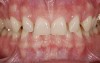

Figure 13  Preoperative photograph of an old, unesthetic PFM

Figure 13

Figure 14  Postoperative photograph of a high-alumina crown system.

Figure 14